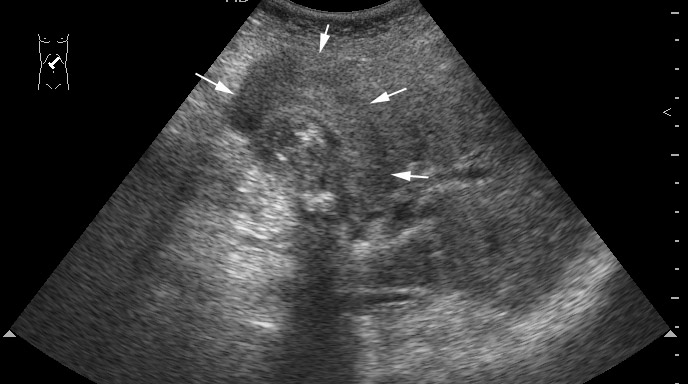

Пожилой мужчина с невыраженными болями в правом подреберье.

Сонограмма

Диагностическая лапаротомия - Рак желчноо пузыря с прорастанием в паренхиму печени

tags: gallbladder, adenocarcinoma, cancer, ultrasonography, CT